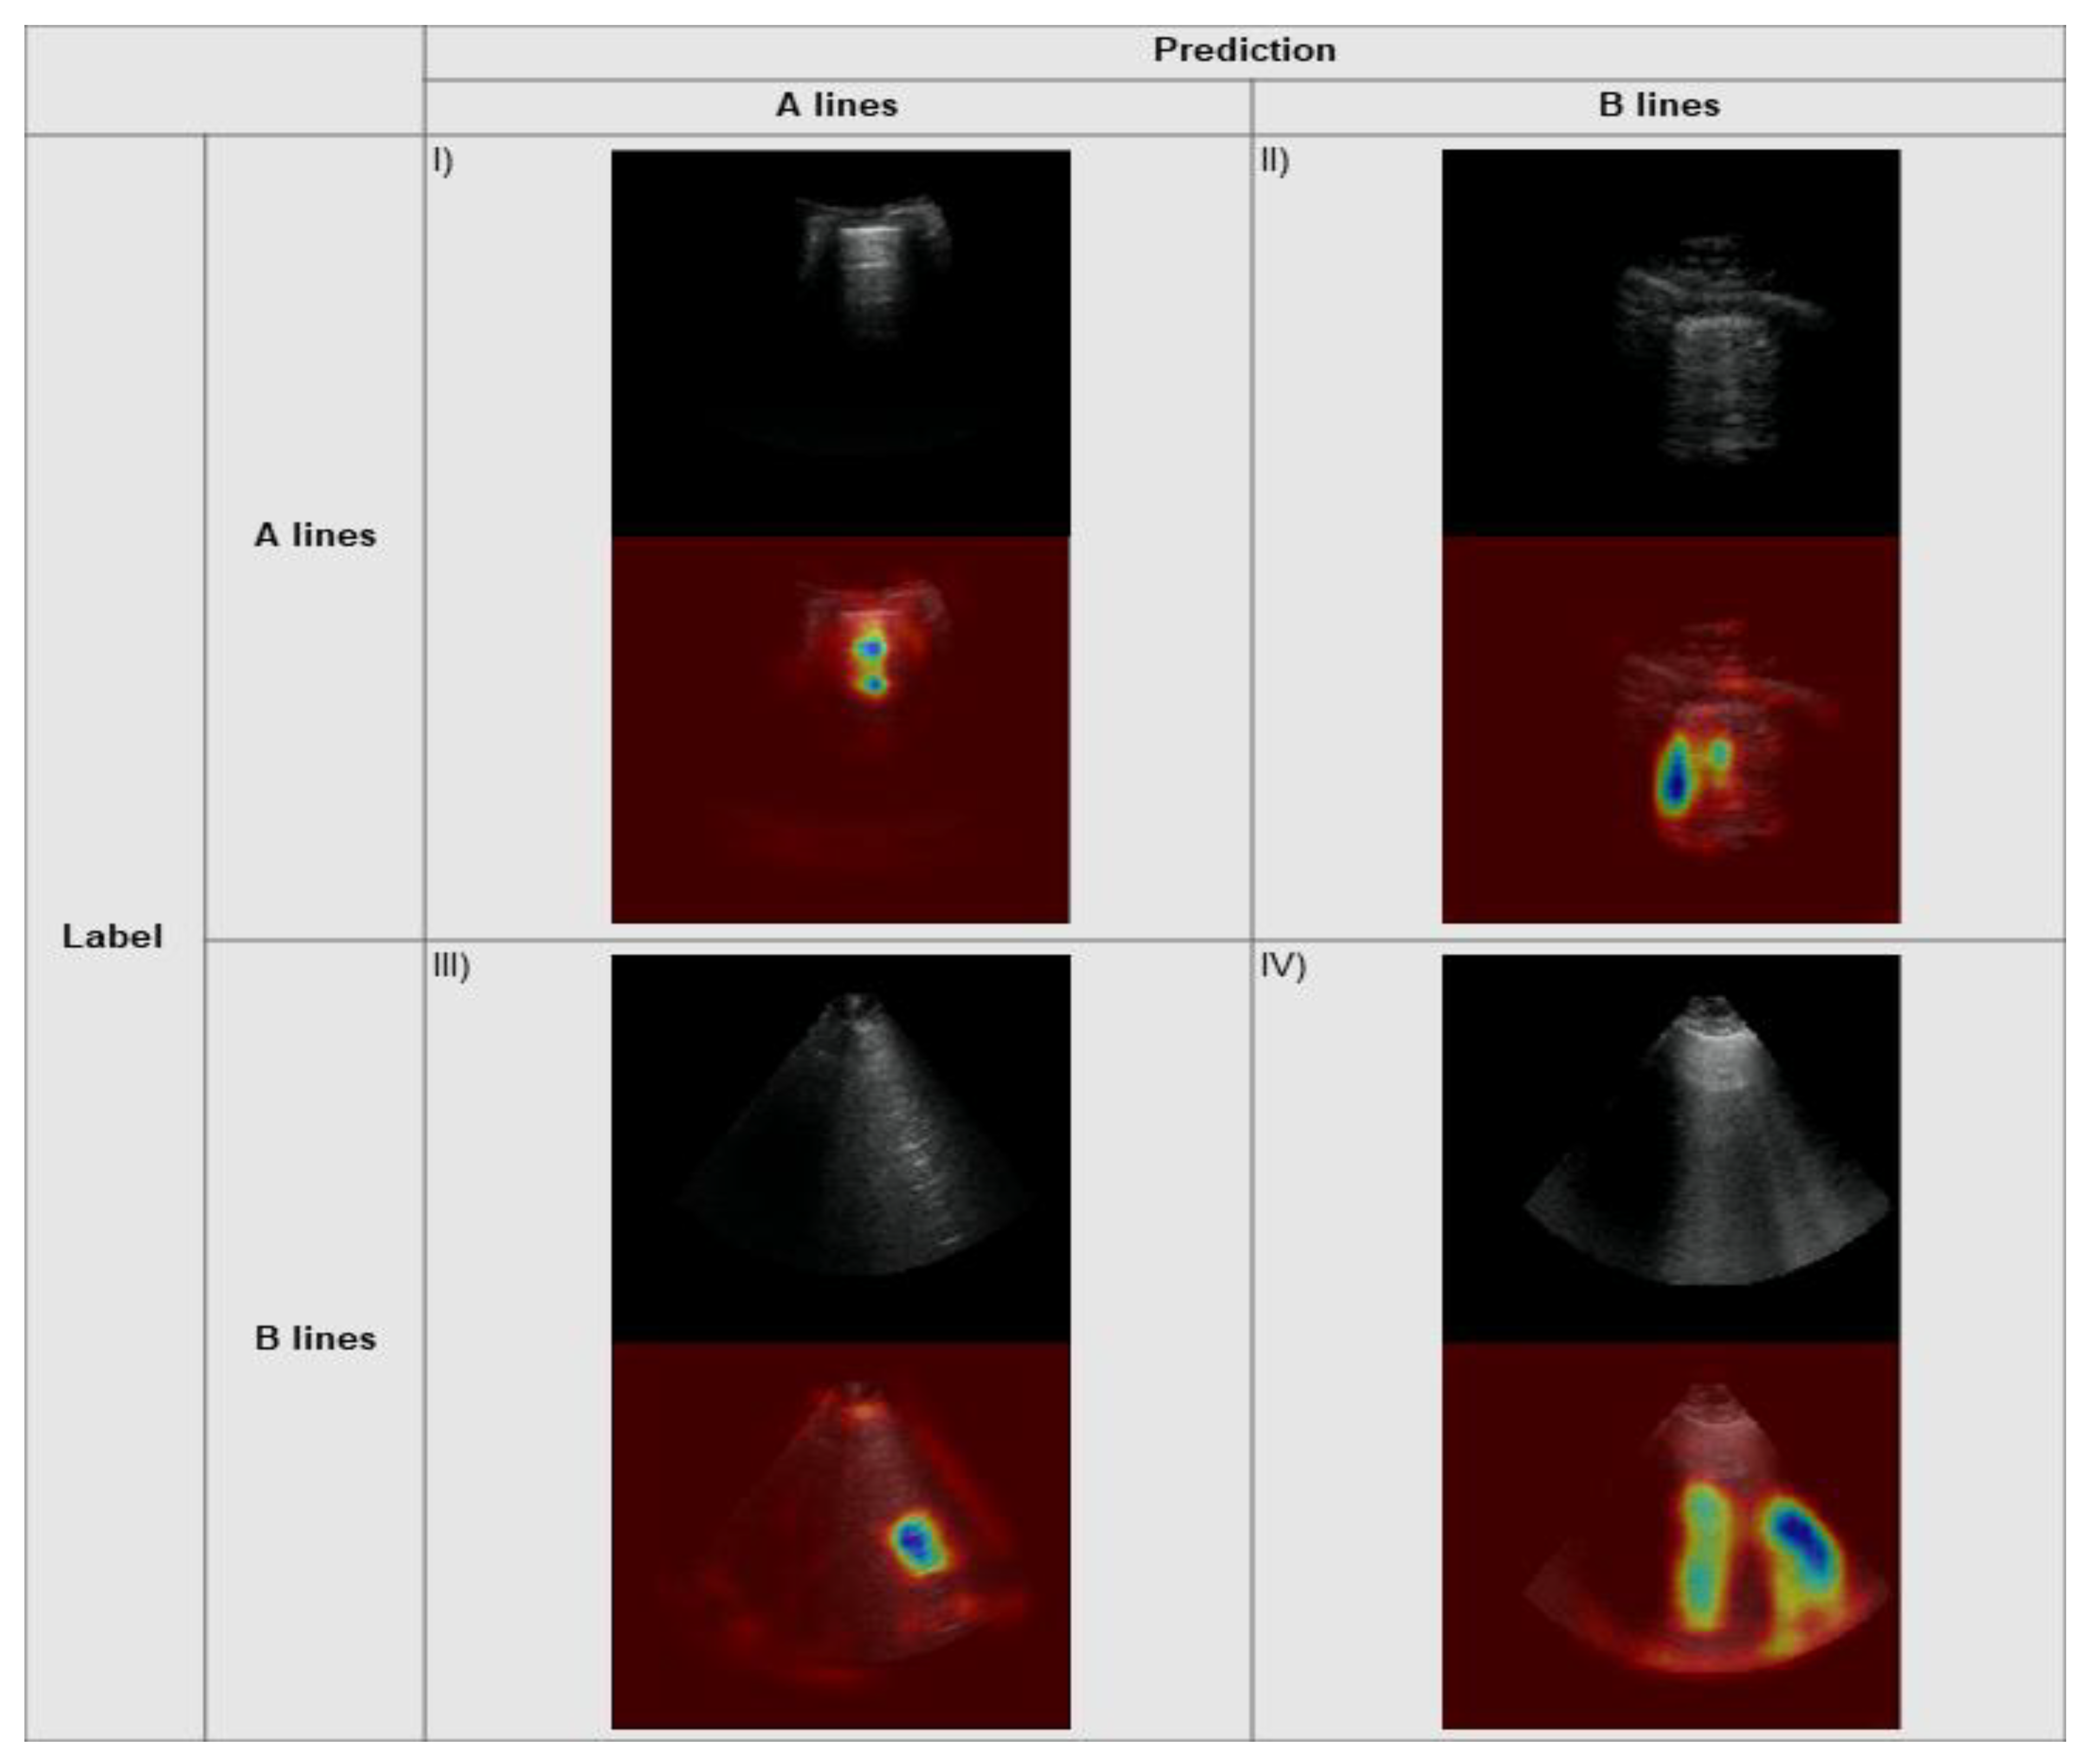

2.5. Explainability

3.3. Explainability